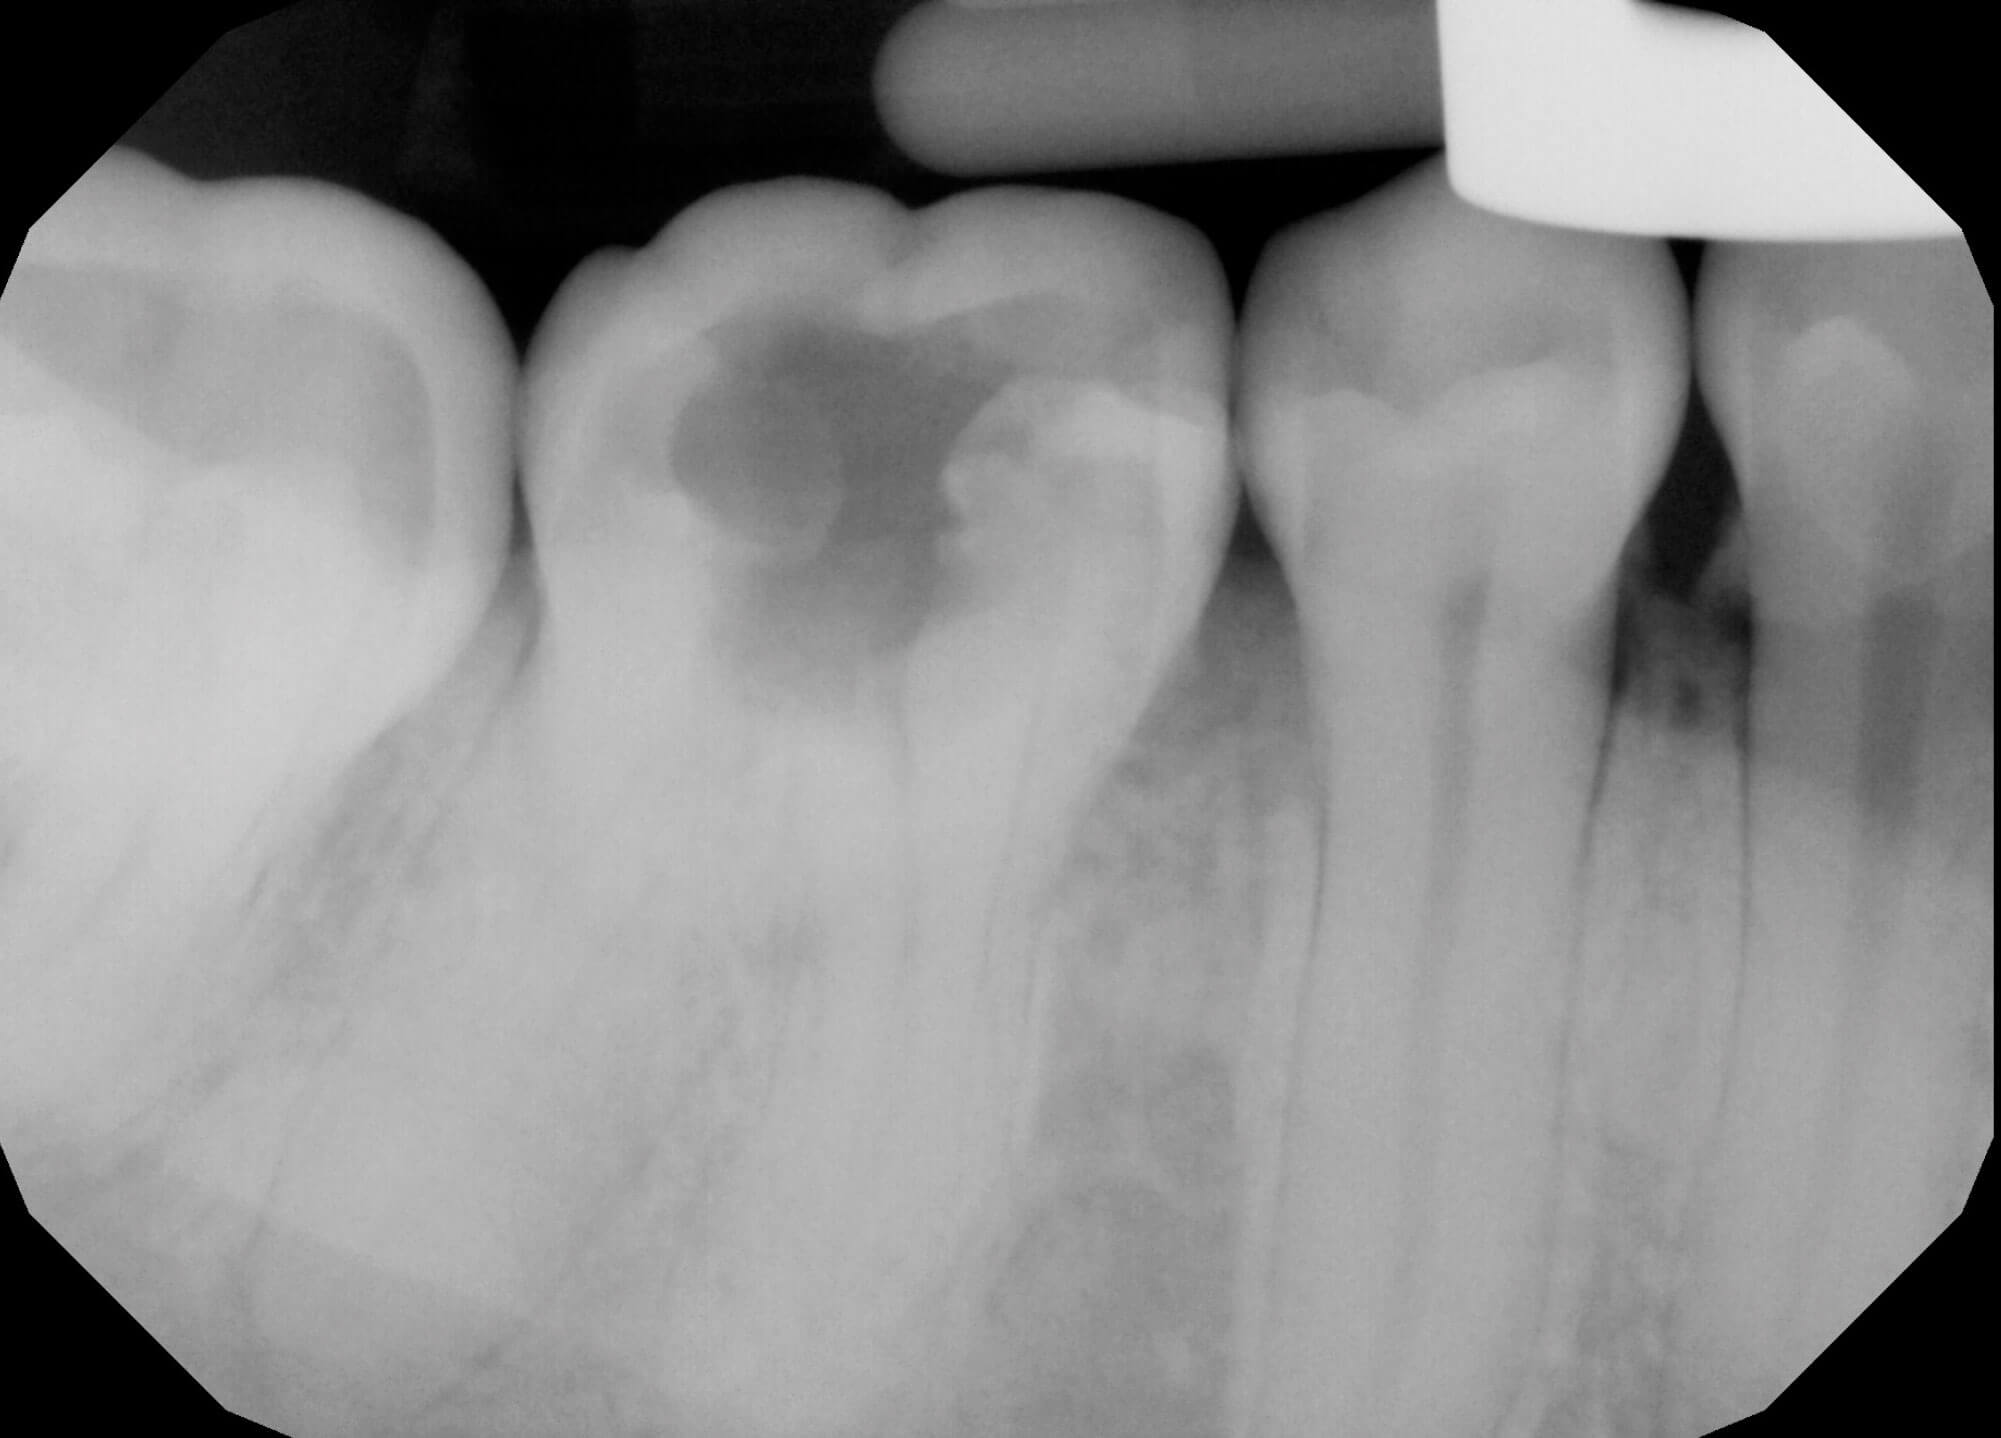

Figure 2: Preoperative radiograph of lower right first molar.

The patient had a lower right first molar extracted one month prior, due to a diagnosis of gross caries and acute apical abscess (Figure 2). They reported pain and swelling from this tooth for several years prior to visiting her general dental practitioner. Medically, she suffers from poorly controlled type-1 diabetes mellitus and takes regular insulin injections with an HbA1c on initial presentation of 91. Socially, the patient is married with two young children, does not drink alcohol but uses e-cigarettes regularly.